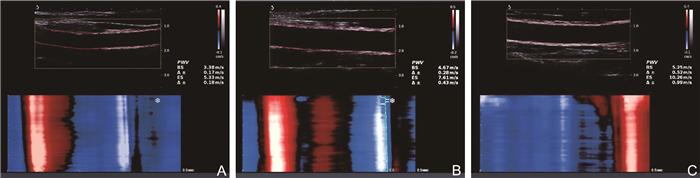

Evaluation of ultrafast pulse wave technique in subclinical atherosclerosis in SLE and its clinical correlates

WANG Xing, LU Fang, SHI Yan, LI Yang, XIE Changhao

2025, 23(7): 1192-1195. doi: 10.16766/j.cnki.issn.1674-4152.004095

311 2

Abstract:

Objective  To make an assessment of vascular elasticity in patients with systemic lupus erythematosus (SLE) at varying levels of disease activity using ultrafast pulse wave technique, and to investigate associated clinical risk factors.  Methods  A total of 116 SLE patients admitted to the First Affiliated Hospital of Bengbu Medical University from October 2020 to April 2024 were selected. Patients were divided into a mild activity group (n=57) and a moderate-to-severe activity group (n=59) according to SLE disease activity index 2000. Additionally, 45 healthy adults were included as the control group. Carotid intima-media thickness (IMT), pulse wave velocity at the beginning of systole (PWV-BS), and pulse wave velocity at the end of systole (PWV-ES) were measured in each group. Clinical data of each group were recorded and analyzed. Carotid artery parameters and clinical data of the three groups were compared to analyze the correlation between PWV parameters and various indicators.  Results  Both PWV-BS and PWV-ES showed significant differences among the three groups, following the pattern: moderate-to-severe activity group > light activity group > control group (P < 0.05). PWV-BS was positively correlated with common carotid artery IMT (r=0.315, P < 0.001), systolic blood pressure (r=0.190, P=0.041), and diastolic blood pressure (r=0.191, P=0.040). PWV-ES was positively correlated with carotid bifurcation IMT (r=0.274, P=0.003), common carotid artery IMT (r=0.361, P < 0.001), and diastolic blood pressure (r=0.252, P=0.006).  Conclusion  The reduction in carotid artery elasticity in SLE patients occurs significantly earlier compared to healthy individuals. Ultrafast pulse wave is valuable, time-independent, and objective tool for quantitative assessing early vascular changes in patients with SLE, thus facilitating the early detection and clinical management of atherosclerosis.